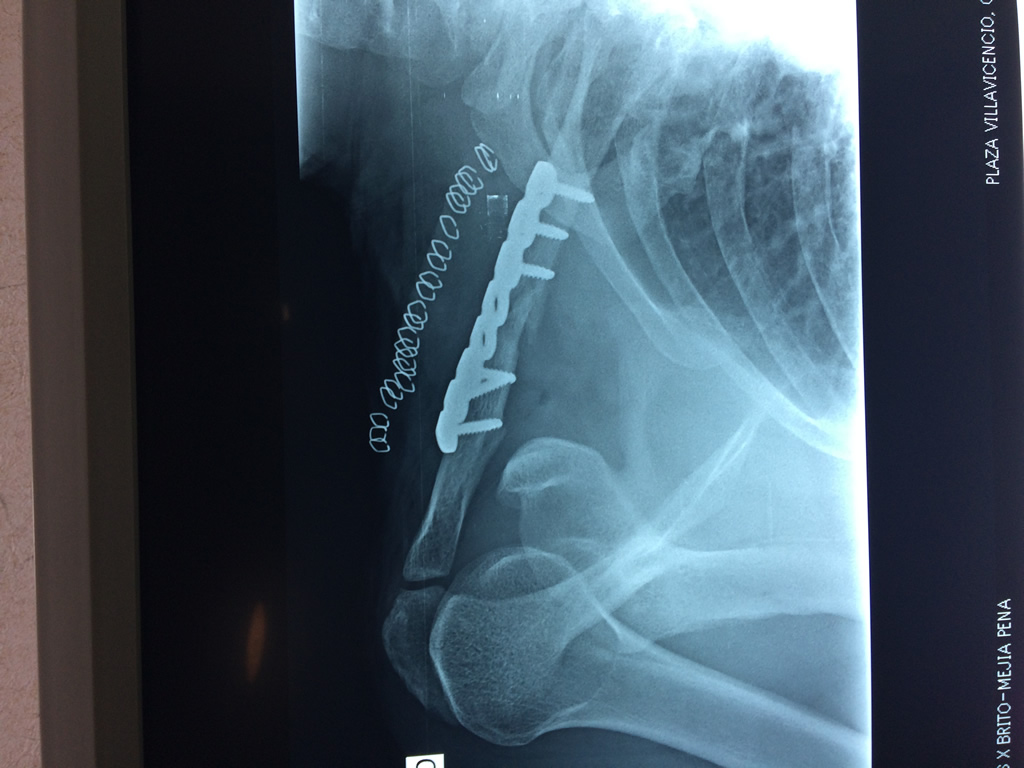

Clavícula

La clavícula es un hueso largo, con forma de "S" itálica, situado en la parte anterosuperior del tórax. Junto con la escápula forman la cintura escapular. Se puede palpar por toda su longitud y se extiende del esternón al acromion de la escápula, siguiendo una dirección oblicua lateral y posterior.